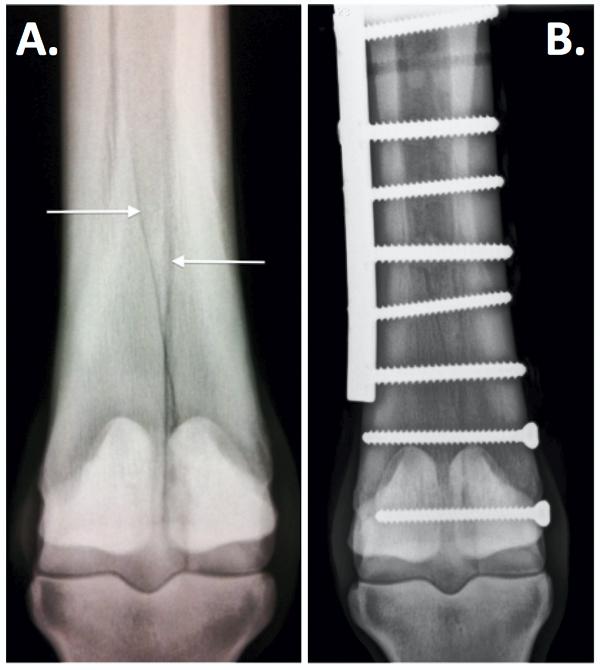

Condylar fractures are the most common long bone fractures in horses. They occur at the bottom of cannon bone where it meets the fetlock joint. They most typically occur in thoroughbred racehorses but are also prevalent in endurance horses and occasionally occur in three-day event horses.